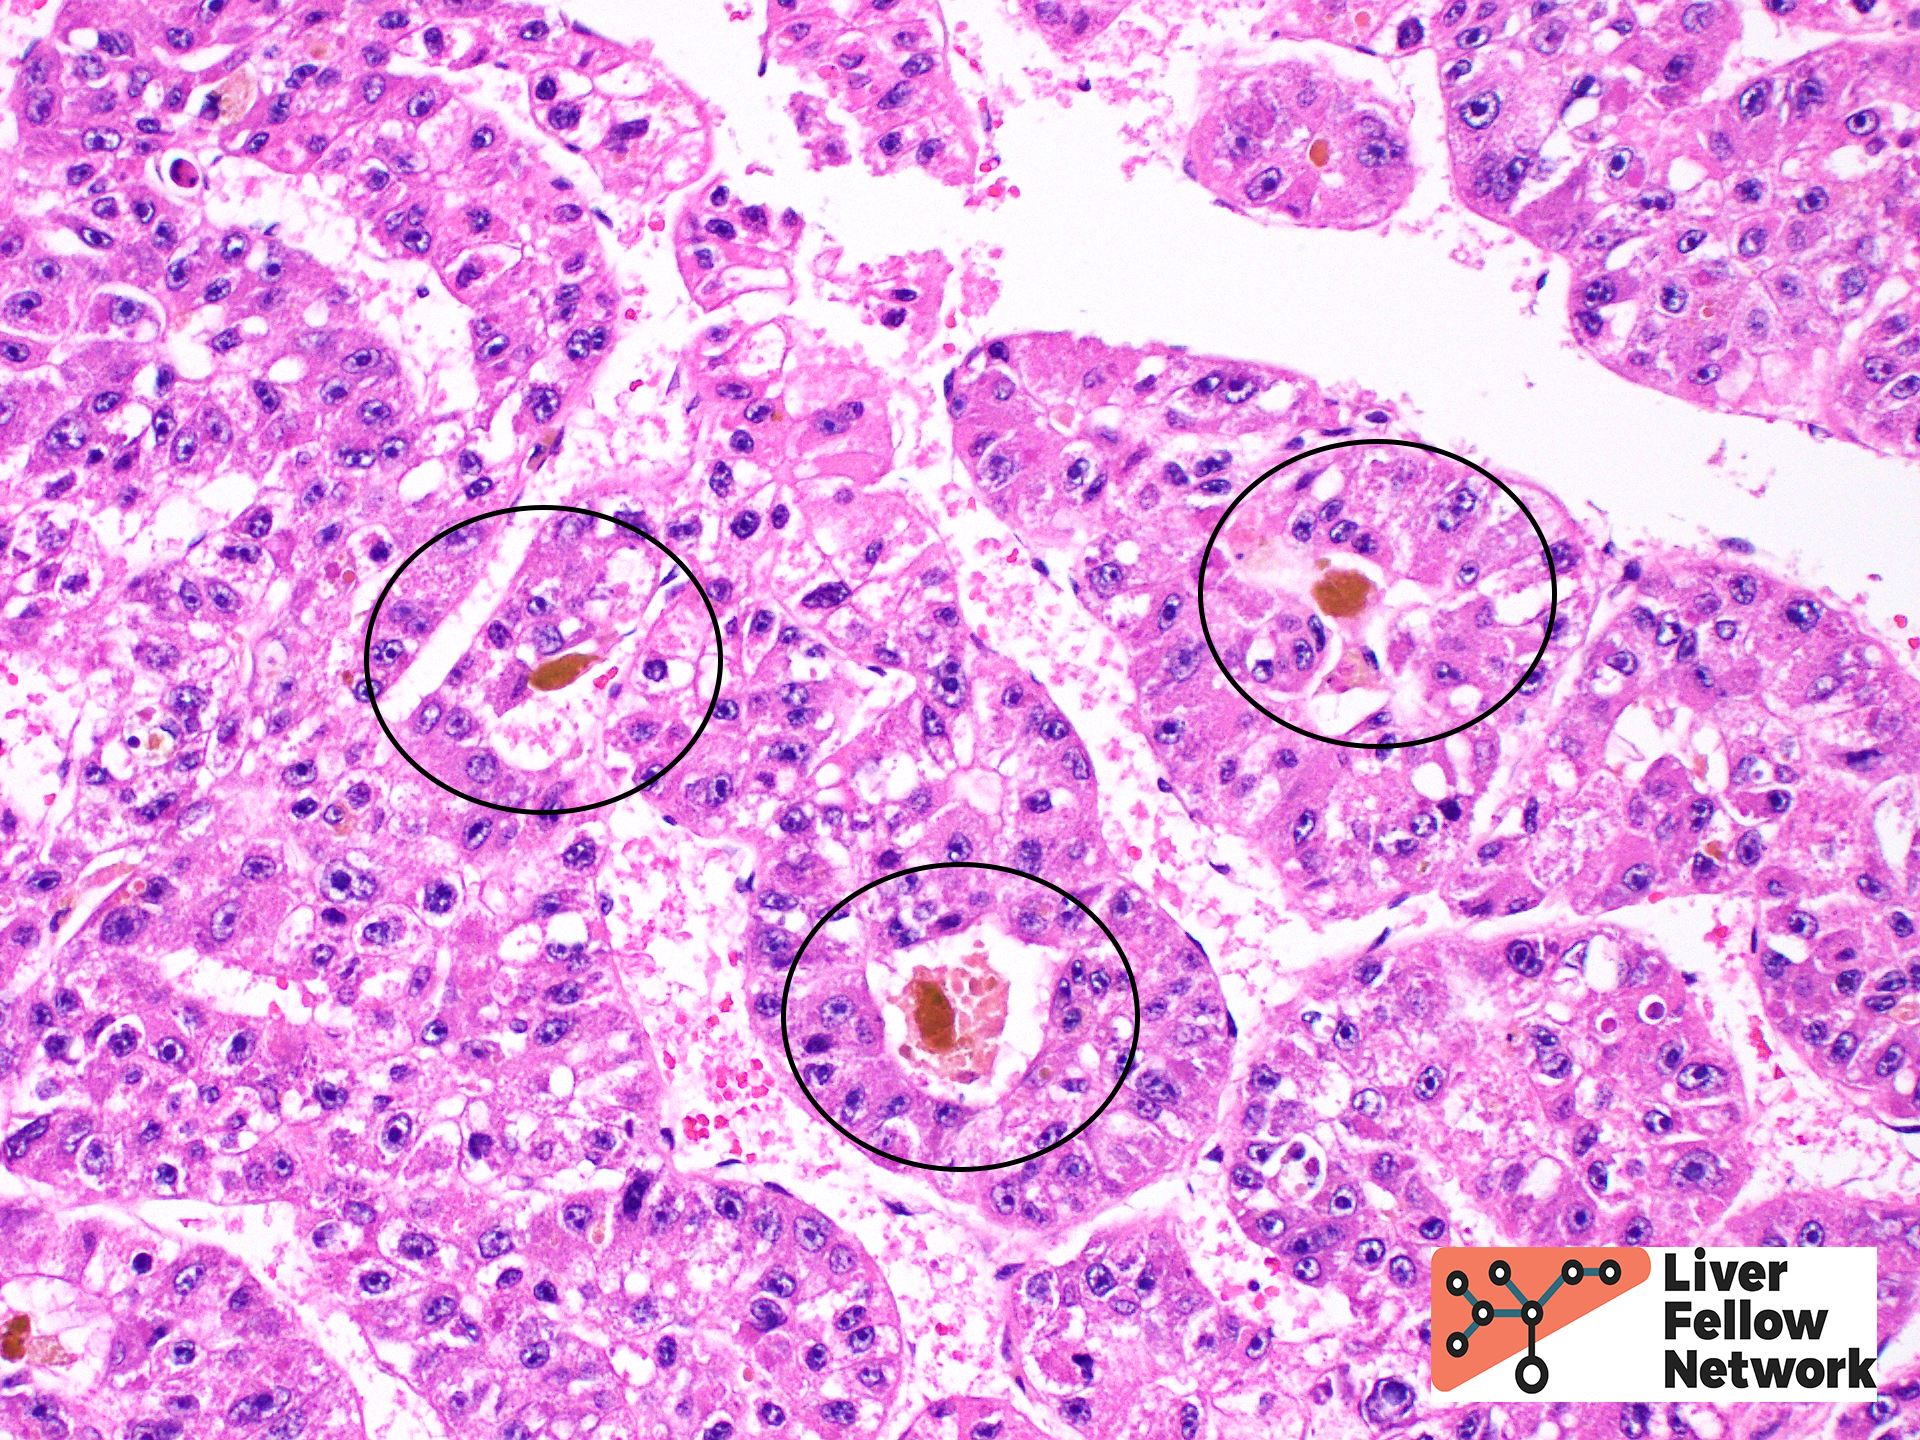

Tumor cell morphology can be helpful, as one can frequently find areas of cytologic atypia (Figure 6, top). Other evidence of hepatocellular differentiation include bile production (Figure 6, bottom).